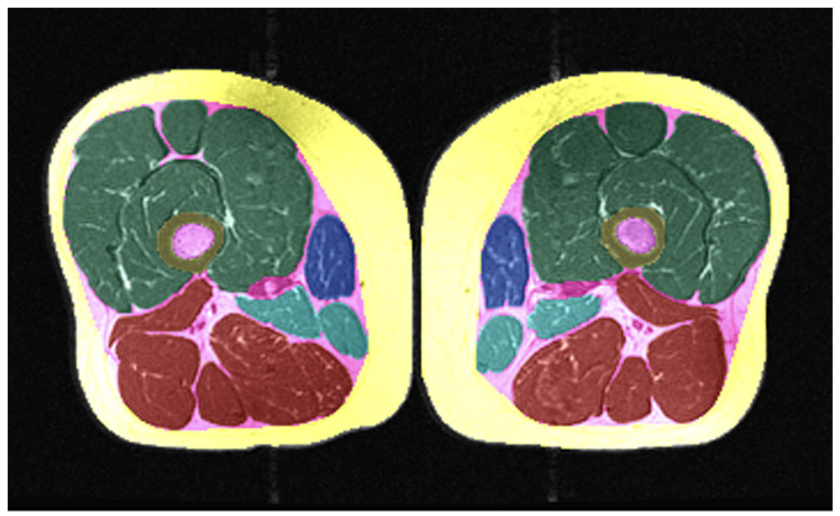

Clinical evaluation of fully automated thigh muscle and adipose tissue segmentation using a U-Net deep learning architecture in context of osteoarthritic knee pain

Jana Kemnitz, Christian F. Baumgartner, Felix Eckstein, Akshay Chaudhari, Anja Ruhdorfer, Wolfgang Wirth, Sebastian K Eder, Ender Konukoglu

Magnetic Resonance Materials in Physics, Biology and Medicine, 33, 483--493 (2020)

Clinical validation of fully automated segmentation of thigh muscle and adipose tissue cross sectional areas using maching learning with a convolutional neural network

J. Kemnitz, Christian F. Baumgartner, A. Ruhdorfer, W. Wirth, F. Eckstein, S.K. Eder, E. Konukoglu

Osteoarthritis and Cartilage, 27, S383-S384 (2019)

journal URL